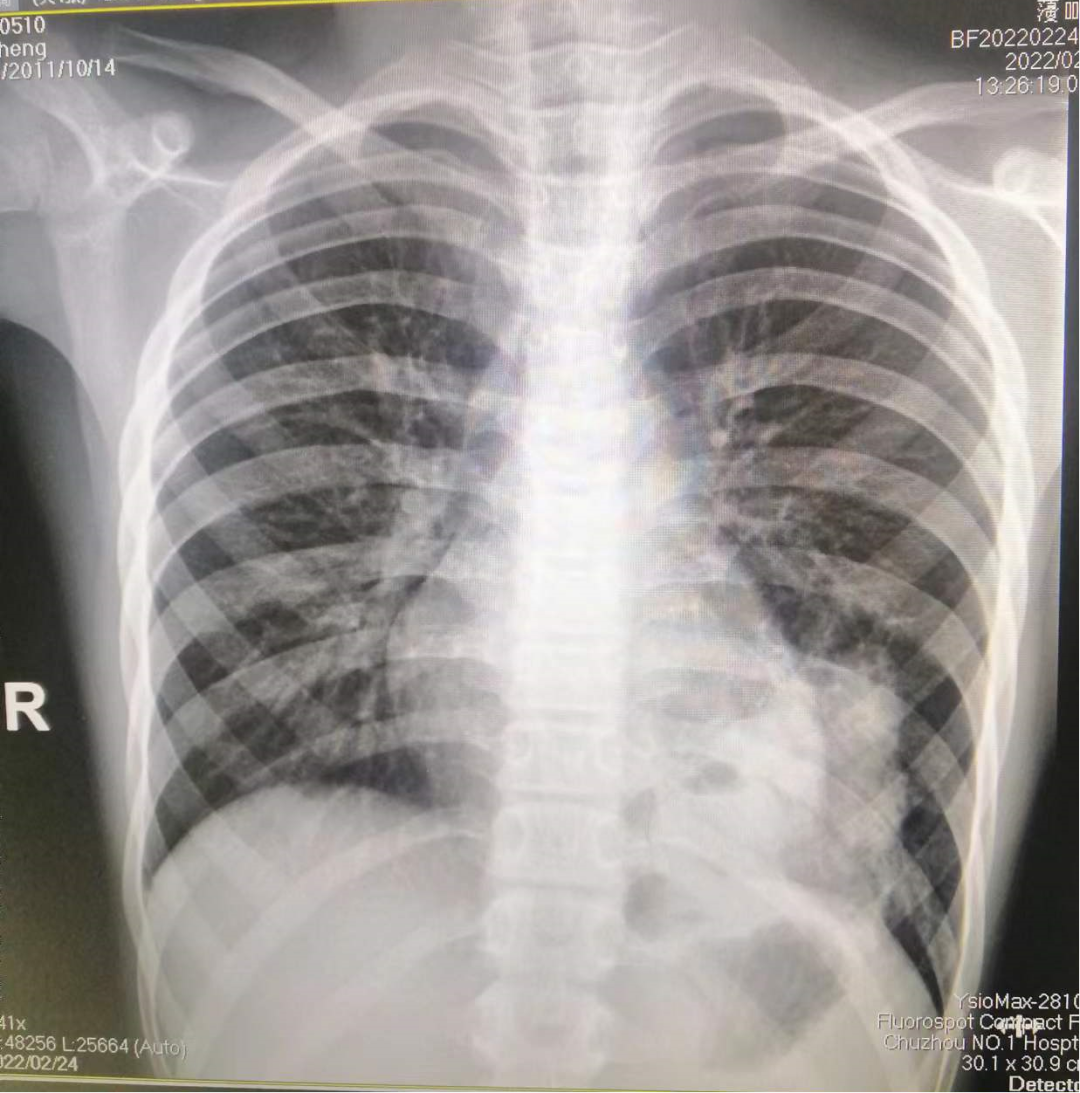

胸片:左下肺可见大片状高密度影,部分与心影重叠,病灶内见气液平影,左侧膈面显示欠清晰,双侧肋膈角锐利。

诊断意见:左下肺病变,考虑炎症性可能性大(如下图1和图2)。

图1-2 患儿入院日胸片及检查所见